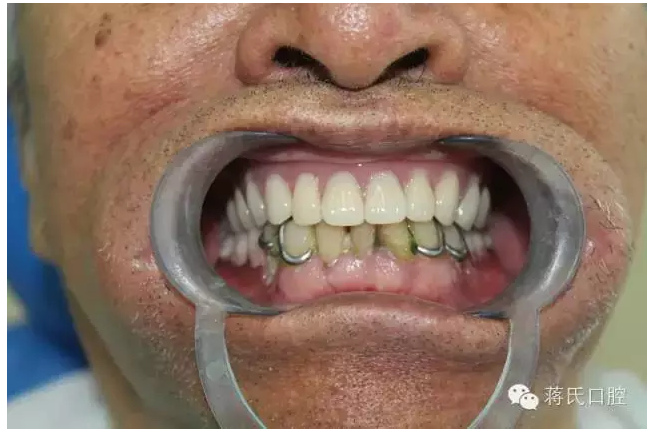

主訴 要求修復(fù)缺失牙,因?yàn)樽陨懋愇锔兄?,已于外院修?fù)幾次義齒,均不能使用,要求花費(fèi)最少的錢解決吃飯問題。

患者情況 男 76歲 ,三類骨。腭咽反應(yīng)重。治療方案 1盡量減少種植費(fèi)用。

4活動義齒雙重冠修復(fù)

5去除上頜基托